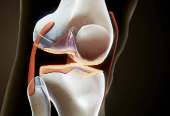

1. 글루코사민이란?

글루코사민은 인체 내에서 자연적으로 생성되는 **아미노당(아미노와 당이 결합된 구조)**으로,

연골, 인대, 힘줄, 활액 등에 존재하며 연골을 구성하고 보호하는 데 핵심적인 역할을 합니다.

① 연골 재생 및 유지

글루코사민은 연골세포 간질 성분인 글리코사미노글리칸의 생성을 촉진하여 연골 재생과 유지를 돕습니다.

연골이 닳는 것을 막고, 마모된 부위의 복구에 기여합니다.

③ 관절 윤활작용 강화

관절 내 활액(윤활유 역할을 하는 액체)의 생성을 도와, 움직임이 더 부드러워지고 마찰을 줄여 관절을 보호합니다.

⑥ 연골 마모 방지

관절에서 연골이 닳아 없으면 뼈와 뼈가 직접 마찰되어 통증이 발생합니다.

글루코사민은 이 연골층의 손상을 늦추고 보완하는 역할을 합니다.